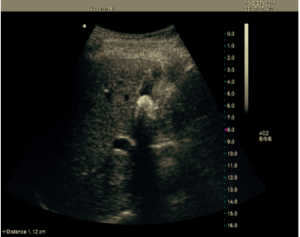

Salve, Ho effettuato un ecografia addome completo, per familiaririta di primo grado (mia madre) per neoplasie della colecisti e pancreas

ll referto riporta nulla da segnalare, tranne

La colecisti che e’

Normoconformata con pareti regolari a parte 2 riverberi a stria di cometa di parete ecopriva

Secondo lei queste strie di cometa nella colecisti, possono essere un segno d’allarme per l’accumulo di calcoli, che con il tempo possono denegerare in una neoplasia